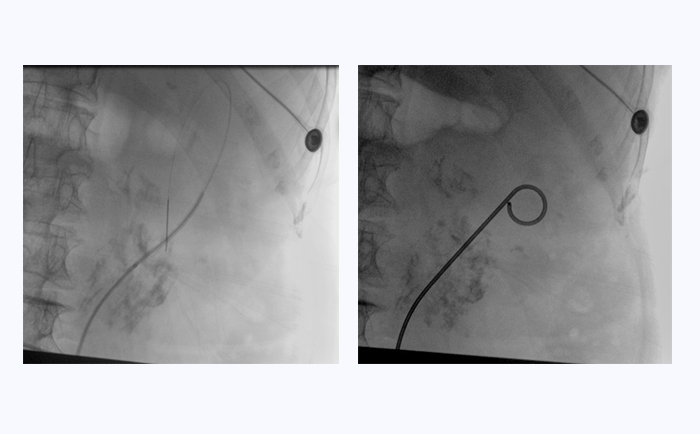

患者采用結(jié)石位進行該手術(shù)。全麻后,操作輸尿管鏡從尿道進入膀胱,通過鏡下觀察,找到輸尿管開口。此時,在普愛醫(yī)療大平板一體式C形臂透視引導(dǎo)下,穿入導(dǎo)絲,到達腎盂并確認(rèn)位置,同時配合輸尿管鏡,找到狹窄部位。接下來,同樣在透視引導(dǎo)下,沿導(dǎo)絲插入雙J管支架,當(dāng)支架兩端到達相應(yīng)位置后,抽出導(dǎo)絲和輸尿管鏡,完成手術(shù)。

普愛醫(yī)療大平板一體式C形臂臨床圖像